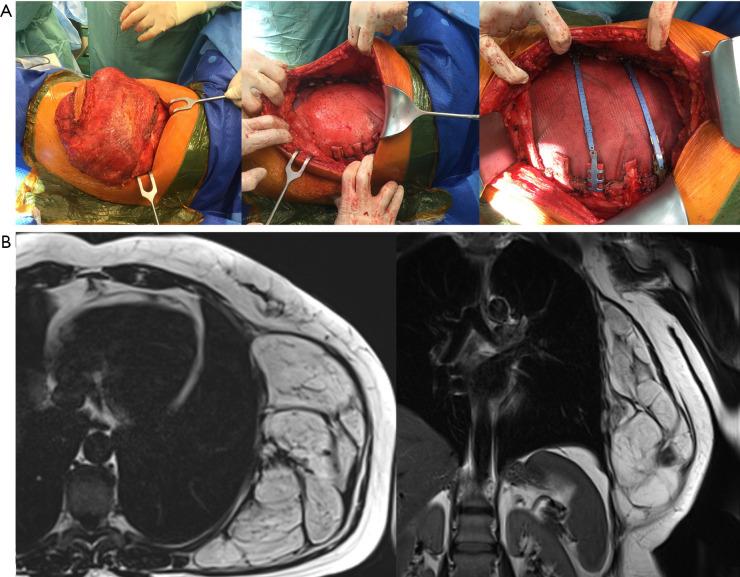

Chest wall sarcomas are rare and pose significant technical challenges in surgical management, particularly in patients with advanced disease. In this study, we examined the extent of resection, reconstruction techniques, and oncological outcomes of patients with chest wall soft tissue and bone sarcomas.

This retrospective single-center series included patients who underwent surgery at our center between May 2014 and February 2022 for deep-seated/subfascial primary and recurrent soft tissue or bone sarcomas of the chest wall requiring significant resection and extensive reconstruction. We analyzed clinical and operative data, including extent of resection, reconstruction techniques, and oncological outcomes. Additionally, we compared survival outcomes between patients with primary and recurrent tumors, and examined how these were influenced by clinical factors using Cox proportional hazards regression analysis.

Of the 38 patients included, 22 were treated for primary or recurrent soft tissue sarcoma (STS) and 16 for bone sarcoma. microscopic radical resection (R0) was achieved in 95.45% and 93.75% of patients with soft tissue and bone sarcomas, respectively. Nonetheless, local recurrence or distant metastases occurred in 40%, 58.33%, and 40% of patients with primary soft tissue, recurrent soft tissue, and bone sarcomas, respectively. Adherence to clinical guidelines and treatment in the reference center was high for bone sarcoma (93.75%), but notably low for STS, resulting in 54.55% of these patients requiring re-resection. Compared with those who underwent only one surgery, patients who underwent re-resection had poorer postoperative outcomes, more severe complications, and longer hospital stay.

Chest wall sarcomas often require extensive resection and complex reconstruction. Although surgical treatment at reference sarcoma centers has significantly improved oncological and clinical outcomes, the prognosis of these patients remains guarded, necessitating further related research and continued refinement in surgical techniques, adjuvant therapies, and follow-up strategies.